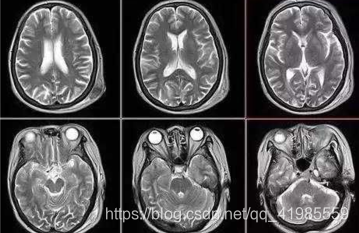

颅脑外伤 ct 与mri影像对比研究

图像处理在医学领域的应用